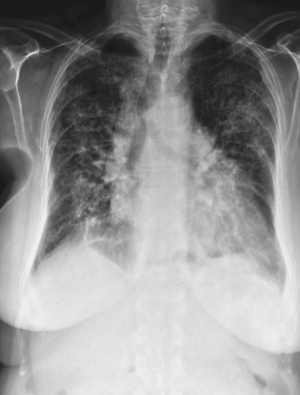

Lung CT Findings

- Ground glass opacities with interstitial or alveolar inflitrations and lung nodules

- Pleural thickening and pleural effusions